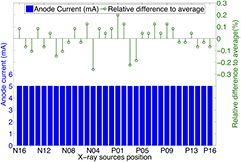

Standard image High-resolution imageThe source-to-source consistency for all 75 CNT x-ray sources was evaluated. The gate voltage needed to generate 5 mA tube current for each source was measured and is plotted in figure 6. All 75 sources output the desired current. The difference between the highest and lowest cathode-gate voltage for 5 mA tube current is approximately 400 V, which was readily compensated for by the control electronics. The source-to-source output consistency in one scan was also evaluated. Figure 7 shows the anode current from each source in a single tomosynthesis scan using 32 CNT x-ray sources. The results show that the CNT source array can output 5 mA anode current consistently from source to source, within 0.3% accuracy. For all the images acquired in this study, all sources were set to output 5 mA tube current. By changing the pulse width (in ms) of each source was on, the x-ray output (in mAs) for each projection image was easily controlled.

Figure 6. Cathode-gate voltages needed to generate 5 mA tube current from each cathode. All 75 CNT cathodes can generate the desired current, with a small variation in voltage from cathode to cathode. The average voltage needed is 1240 V. The P00 refers to the central beam source, while the P and N notate positive and negative locations of the source relative to the central beam, respectively.

Standard image High-resolution imageFigure 7. Summary of anode current in a short tomosynthesis scan using 32 sources and the relative difference to the average anode current. The CNT source array consistently output 5 mA from source to source with relative difference within 0.3%.